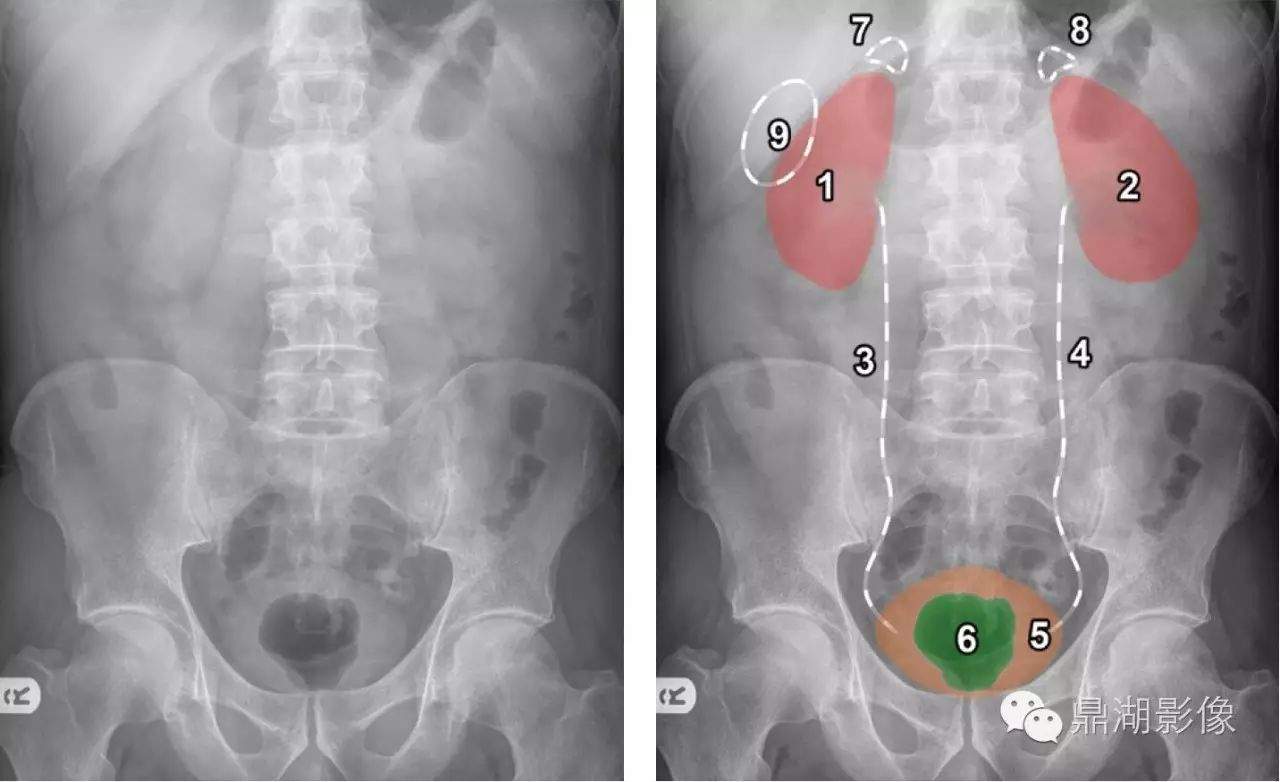

影像基础 正常腹部x线学习

腹部x光,女性腹部x光